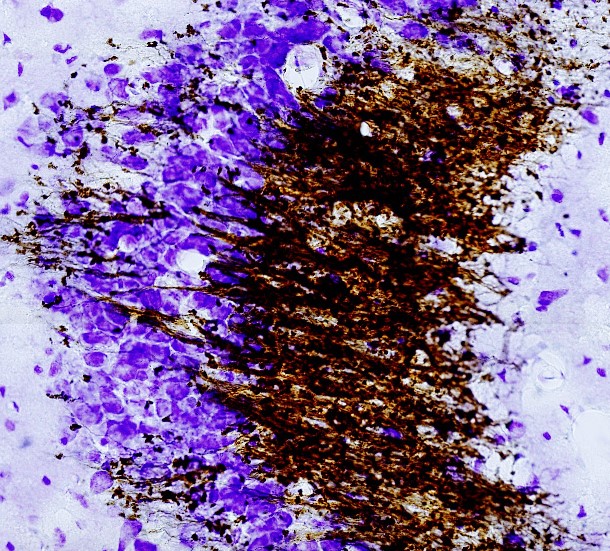

- Neurobiology of microglial and astroglial cells